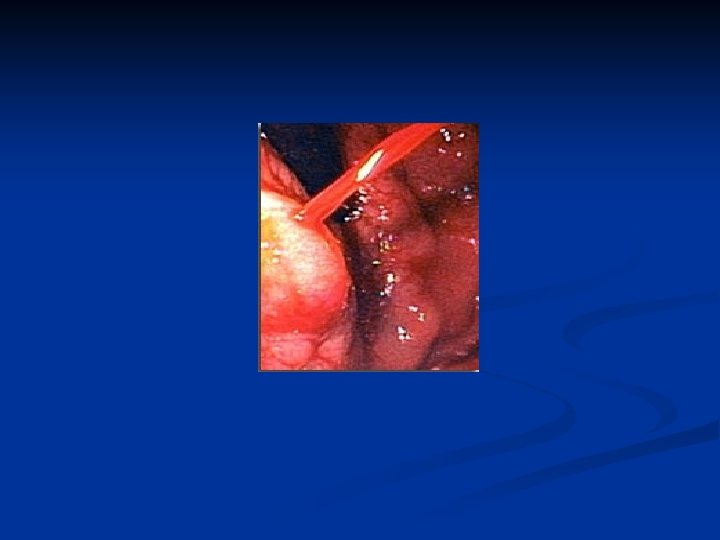

Signes cliniques HTP n Varices oesophagiennes Endoscopie n 1/3 < œsophage n Réseau de petites veines dans la lamina propria n HTP > 12 mm Hg (risque hémorragique) n Taille (pas de corrélation entre taille et pression portale), extension, couleur, signes rouges (dilatation vasculaire) : stries, tache maculaire, télangiectasie (haut risque de saignement 80 %) n

Varices oesophagiennes